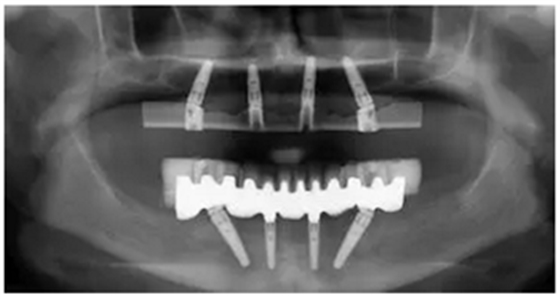

手術(shù)后90天拍攝連帶內(nèi)錐形連接愈合基臺的X光片。

手術(shù)后16周最終修復(fù)X光片:計算機(jī)輔助導(dǎo)板引導(dǎo)種植能夠保證在All-on-4治療中精準(zhǔn)安全地植入軸向和傾斜植體。